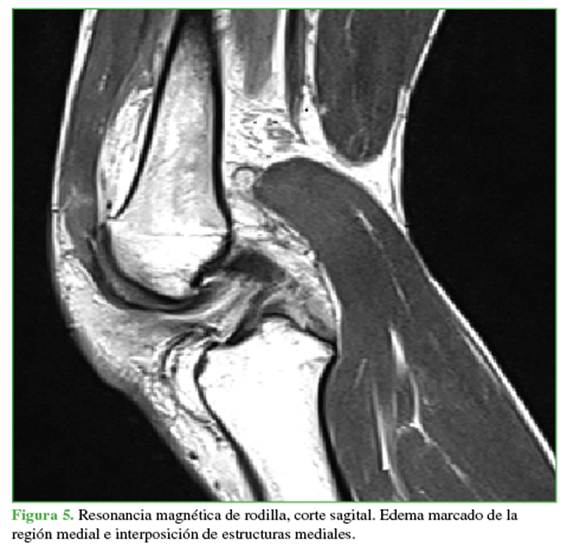

Las radiografías mostraban un aumento del espacio medial debido a la inestabilidad medial. Se ampliaron los estudios con una resonancia magnética (Figuras 4 y 5) para evaluar posibles tejidos o estructuras interpuestos y con una angiotomografía (Figura 6) para descartar una lesión vascular por el tiempo de evolución. Se observó un gran edema en los tejidos mediales, inclusive la cápsula y los tejidos mediales en la zona intercondílea, así como una persistente subluxación de la rodilla. Se descartó un compromiso vascular con integridad del paquete femoropoplíteo.

Se presenta a un paciente con luxación irreductible de rodilla, lesiones de múltiples ligamentos y luxación de rótula tras caer por un abismo. Tiene el signo del hoyuelo. Se intentaron varios métodos de reducción cerrada sin éxito, lo que requirió una reducción abierta para exponer y liberar las estructuras interpuestas, inclusive la cápsula medial, el ligamento rotulofemoral y el vasto medial oblicuo. Se colocó un inmovilizador de rodilla y se esperó hasta que los tejidos blandos mejoraran para realizar una reconstrucción de múltiples ligamentos en un segundo tiempo, abordando los ligamentos cruzados anterior y posterior, y la esquina posteromedial; el resultado fue favorable. Conclusiones: Se recomienda, en primera instancia, la reducción cerrada, pero si las estructuras mediales de la rodilla no se liberan, es necesaria la reducción abierta de emergencia. La reconstrucción ligamentaria se indica cuando hay compromiso de múltiples ligamentos, y la elección del abordaje del ligamento cruzado debe individualizarse considerando la edad, el estado fisiológico y las actividades físicas del paciente. Además, es crucial realizar una evaluación neurológica y vascular exhaustiva ante el riesgo de complicaciones graves. Se comunica este caso para destacar este cuadro inusual y la importancia de una reducción abierta para lograr una reducción adecuada.